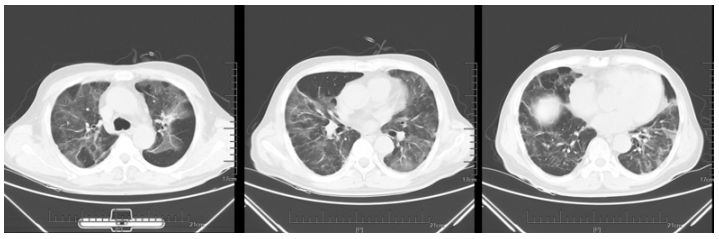

1月17日复查胸部CT:双肺磨玻璃影较前有所吸收(图2)

图2  复查胸部CT(2023-01-17)

转入我科后患者体温热峰似乎有所下降,但仍有低热。1月27日复查胸部CT可见新冠肺炎病灶吸收、空洞形成,其中见小结节。支持真菌感染(图3)

图3  复查胸部CT(2023-01-27)